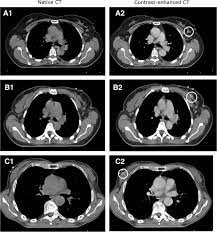

Ct scans can help doctors: If you have a large breast cancer, your doctor may order a ct scan to assess whether or not the cancer has moved into the chest wall. This substance is often called a tracer, because it helps reveal cancer in the body. The scan lets them:learn the cancer's stage. Computed tomography scan, ct scan, cat scan, and spiral or helical ct. 234 views answered >2 years ago Before the scan, you will either drink a liquid dye or be given an injection of dye into a vein in your arm. Breast cancer affects over 200,000 women each year. A pelvic ct scan can be used to detect several types of cancer. Contrast medium is a dye that helps body tissues show up more clearly on the scan. In contrast with bone scans, which are only able to detect bone metastases, pet/ct has the advantage of concurrently imaging other common sites of breast cancer metastases such as the liver and lungs, says lead author patrick morris, a breast cancer specialist at memorial sloan kettering. You are encouraged to drink clear liquids. This helps determine whether or not the cancer can be removed with mastectomy.

In general breast cancer can be detected on a routine chest ct scan regardless of if contrast media is used or not. Several types of cancer can form in the breast, making it the second most common cancer that affects american women. These scans expose you to more. Before a pet/ct scan, an iv that injects a small amount of a radioactive substance will be placed into one of your veins. Long story short i have a ct scan with contrast on 1st june to look for cancer in the abdominal cavity.

Advanced Radiology Consultants Fast Breast Mri from www.adrad.com The term tomography comes from the greek words tomos (a cut, a slice, or a section) and graphein (to write or record). They may also use it to learn more about the cancer after they find it. If i had contrast on the earlier ct, my cancer would have been found 2 1/2 years earlier. When a ct scan misses cancer. Breast cancer affects over 200,000 women each year. If you have a large breast cancer, your doctor may order a ct scan to assess whether or not the cancer has moved into the chest wall. A ct scan may be used to: Therefore, ct scans can lead to a false negative this can negatively impact your ability to get any treatment at all this can prolong the time it takes you to access treatment

95% of nodules found are benign. Learn the stage of your cancer. Long story short i have a ct scan with contrast on 1st june to look for cancer in the abdominal cavity. Doctors use a computed tomography (ct) scan, also called a cat scan, to find cancer. The scan is painless and takes about 10 to 30 minutes. Other names for this test: In general breast cancer can be detected on a routine chest ct scan regardless of if contrast media is used or not. Learn more about it on our blog. The term tomography comes from the greek words tomos (a cut, a slice, or a section) and graphein (to write or record). Amongst everything that's been going on i have not been checking my breasts, stupidly i was looking for cancer in other areas and now i think my breast may be the culprit. The scan is painless and usually takes between 5 to 30 minutes. Are you preparing to have this procedure soon? Before the scan, you will either drink a liquid dye or be given an injection of dye into a vein in your arm.